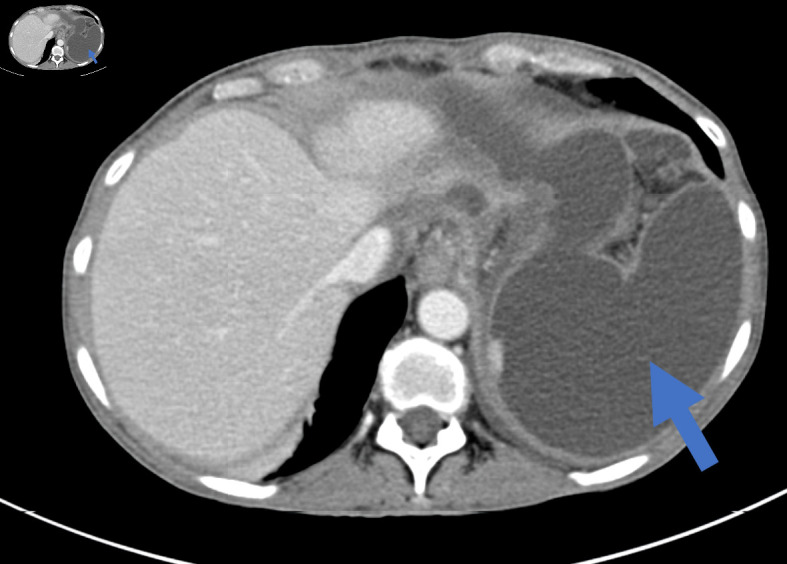

Pancreatoduodenectomy (PD) is a very complex and highly challenging operation for surgeons worldwide. It is the surgical procedure of choice for the management of benign and malignant diseases of the periampullary region. Although mortality rate following this complicated surgery has fallen to 1-3%, morbidity rate following PD remains high, with almost 30-40% of patients developing at least one complication. Postoperative pancreatic fistula (POPF) is one of the most common complications following PD. Therefore, Pancreatico-enteric anastomosis has been regarded as the "Achilles heel" of the modern, one-stage PD procedure. According to the International Study Group of Pancreatic Surgery (ISGPS), three types of POPF are recognized nowadays: biochemical leak, previously known as grade A POPF, grade B and grade C, with the latter being the most dangerous. Most POPFs, especially of the biochemical leak and grade B heal with non-operative management to recur later and present as an intra-abdominal abscess or pseudocyst, necessitating management by means of interventional radiology, endoscopy or surgery. These types of fistulas are undefined and occasionally intractable. Herein, we present two patients who presented with the aforementioned type of pancreatic fistula following duct occlusion PD. The first patient, a 53-year-old female patient, suffered from intolerance to oral feeding, severe weight loss and recurrent hospital admission, while the second patient, a 72-year-old patient, suffered from recurrent bouts of abdominal sepsis. Their management involved step-up approach, starting with non-operative management, followed by percutaneous drainage and operative treatment in the form of Puestow-like procedure (longitudinal pancreatojejunostomy), as a recourse due to the inadequacy of preceding therapeutic modalities.

Abstract Image